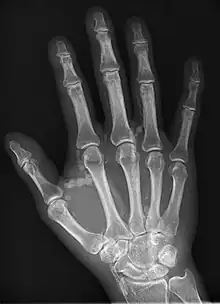

Hand radiograph showing tumoral calcinosis, PA radiograph of the right hand showing tumoral calcinosis-like metastatic calcification in a patient on dialysis. Dialysis alters calcium phosphate product (>70). Idiopathic tumoral calcinosis is autosomal dominant and is not associated with dialysis. Note the premature arterial calcification which is a clue that this is a renal patient. Vascular calcification contributes to an increase in morbidity. |

Tumoral calcinosis is a rare condition in which there is calcium deposition in the soft tissue in periarticular location, around joints, outside the joint capsule.[1] They are frequently (0.5–3%) seen in patients undergoing renal dialysis. Clinically also known as hyperphosphatemic familial tumoral calcinosis (HFTC), is often caused by genetic mutations in genes that regulate phosphate physiology in the body (leading to too much phosphate (hyperphosphatemia)). Best described genes that harbour mutations in humans are FGF-23,[2] Klotho (KL),[3] or GALNT3.[4] A zebrafish animal model with reduced GALNT3 expression also showed HFTC-like phenotype,[5] indicating an evolutionary conserved mechanism that is involved in developing tumoral calcinosis.